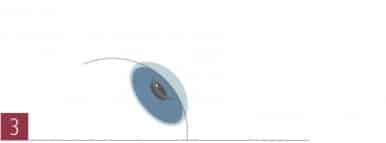

Die Ringe “straffen” den vorherigen Hornhautkegel und schaffen eine regelmäßigere Hornhautoberfläche.

Die Ringe “straffen” den vorherigen Hornhautkegel und schaffen eine regelmäßigere Hornhautoberfläche.